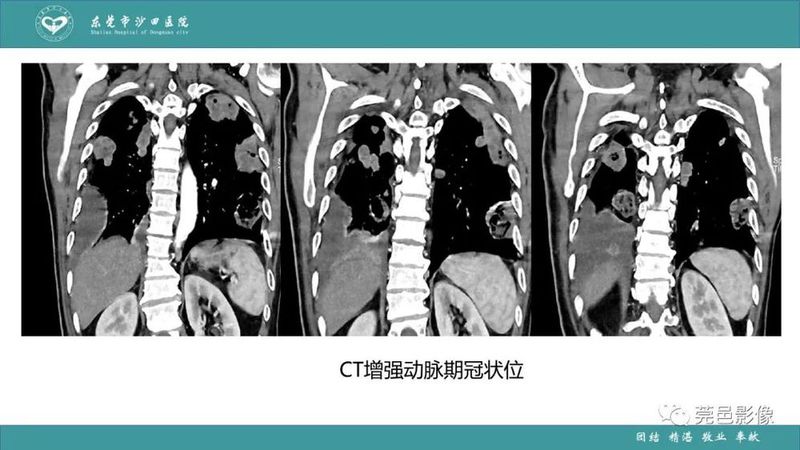

「肺炎克雷伯杆菌肺炎」影像学诊断+鉴别诊断